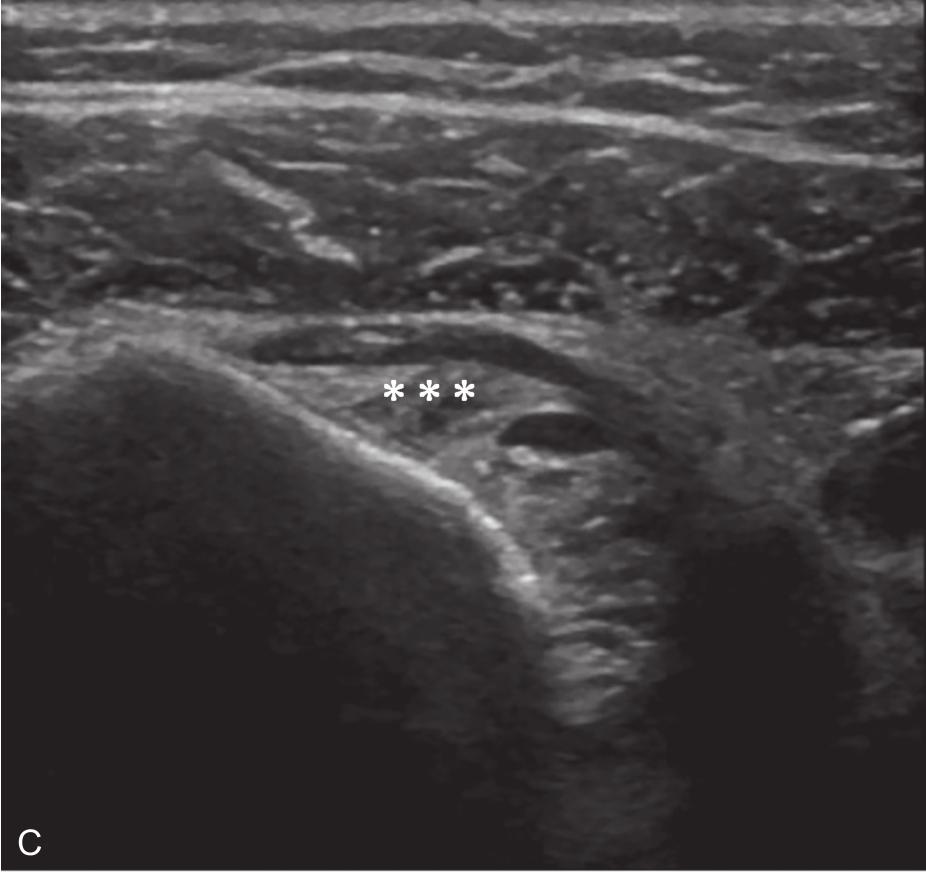

▲ 图2-6-6 超声引导下肩关节腔介入治疗超声图(四)

A.超声引导下穿刺针进入盂肱关节;B.注射治疗后扩张的关节腔;C.注射治疗后关节腔内粘连带;单星号:关节腔;三星号:关节腔内粘连带;箭头:穿刺针